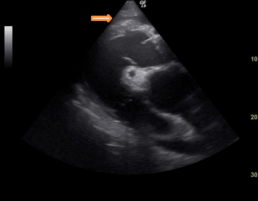

Elektro- und echokardiographische Untersuchung

Es wurde eine mittelgradige Aortenklappeninsuffizienz festgestellt. (Abb. 1+2)

Abb.1: 4-Kammerblick rechts

Abb.2: RKDLA mittelgradige Aortenklappeninsuffizienz